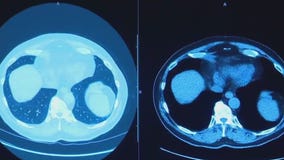

Lung cancer survivor in Austin advocates for screening, detection

An Austin man went to the doctor complaining of one problem. But, a CAT scan revealed another bigger concern: lung cancer.